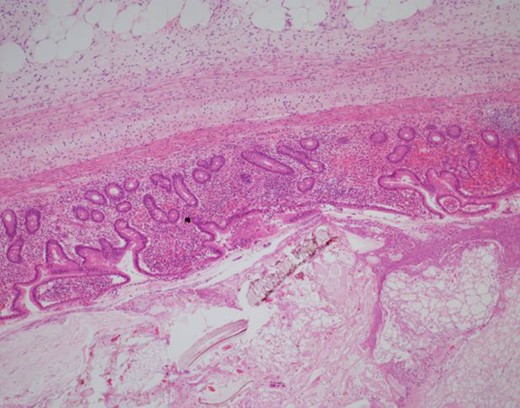

During the exploratory laparotomy, the segment of small bowel with the inflammatory phlegmon was noted and withdrawn from the surgical site for inspection. An isolated segment of bowel measuring ~20 cm was resected between and a side-to-side functional and end anastomosis was created. The surgical findings included a solitary diverticulum at the mesenteric aspect of the bowel with marked erythema, induration and slight exudate at the proximal jejunum. There was no evidence of diverticular perforation. Pathology revealed the serosal surface of the jejunum was notable for a 2.5 cm region of protrusion associated with congestion, exudation and possible hemorrhage; when the resected segment of small bowel was opened, there was a prominent fecal filled diverticulum corresponding to the focus of serosal protrusion (Figs 2–4).

H&E 1× image of the small bowel diverticulum (top of image) pouching out from the bowel lumen (bottom of image).

H&E 40× image of the mucosal lining of the diverticulum and ingested food debris in the lumen. Only the mucosa is present in the wall, which classifies this as an acquired rather than congenital.